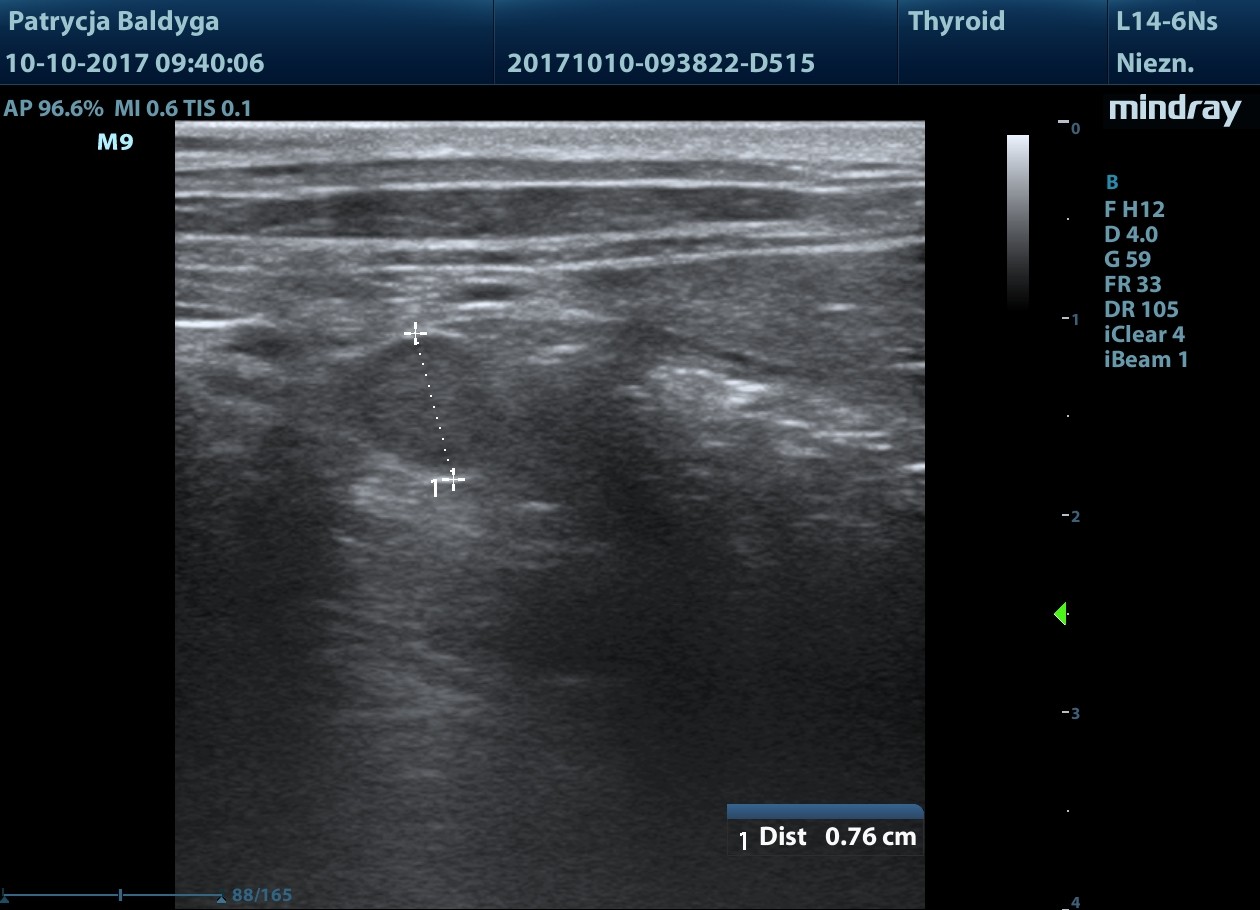

w końcowym odc. okręznicy poprzecznej nadśledzionowo widoczna zmiana ogniskowa

naciekowa, śródścienna, hipoechogenna, niesymetryczna 6-18 mm, dł. 2,5 cm, warstwowość w tym miejscu zatarta, obecny okoliczny, nieznaczny odczyn zapalny (pod koniec filmu 3), ww, chłonne okrężnicze środkowe reaktywne, powiększone, hipoechogenne, zokrąglone, śr. ok. 7-8 mm